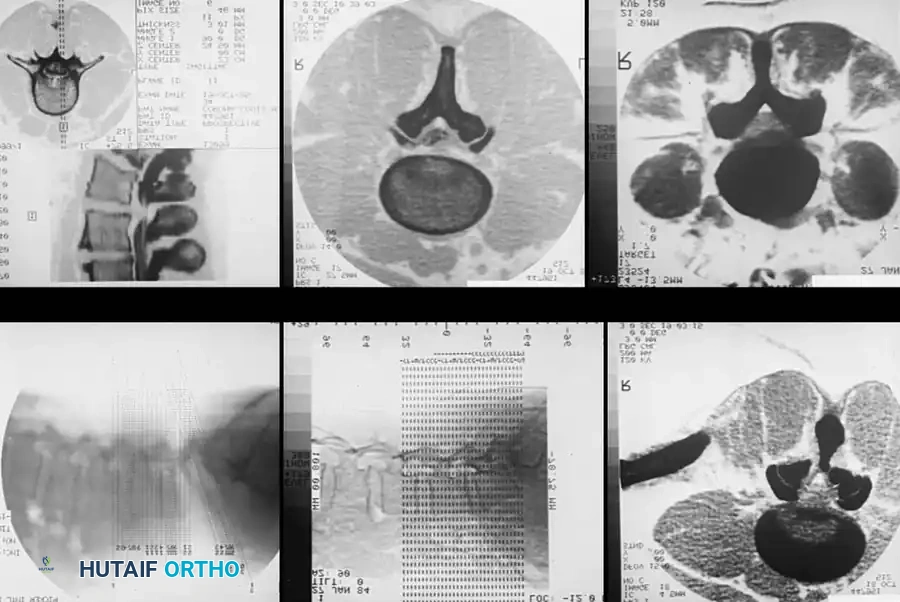

DIAGNOSTIC STUDIES Surgical Diagram

Fig. 39-6 D: Postmyelogram CT axial cut. The introduction of intrathecal contrast provides stark differentiation between the thecal sac, nerve roots, and surrounding osseous structures.

Fig. 39-6 E: Postmyelogram CT clearly revealing a right intraforaminal disc herniation compressing the exiting C7 nerve root, which was missed on the initial MRI.

Studies by Bell et al. found myelography to be more accurate than standard CT scanning for identifying HNP, and slightly more accurate for detecting spinal stenosis. While Szypryt et al. noted myelography is slightly less sensitive than MRI for general spinal abnormalities, its specificity in the presence of hardware is unmatched.